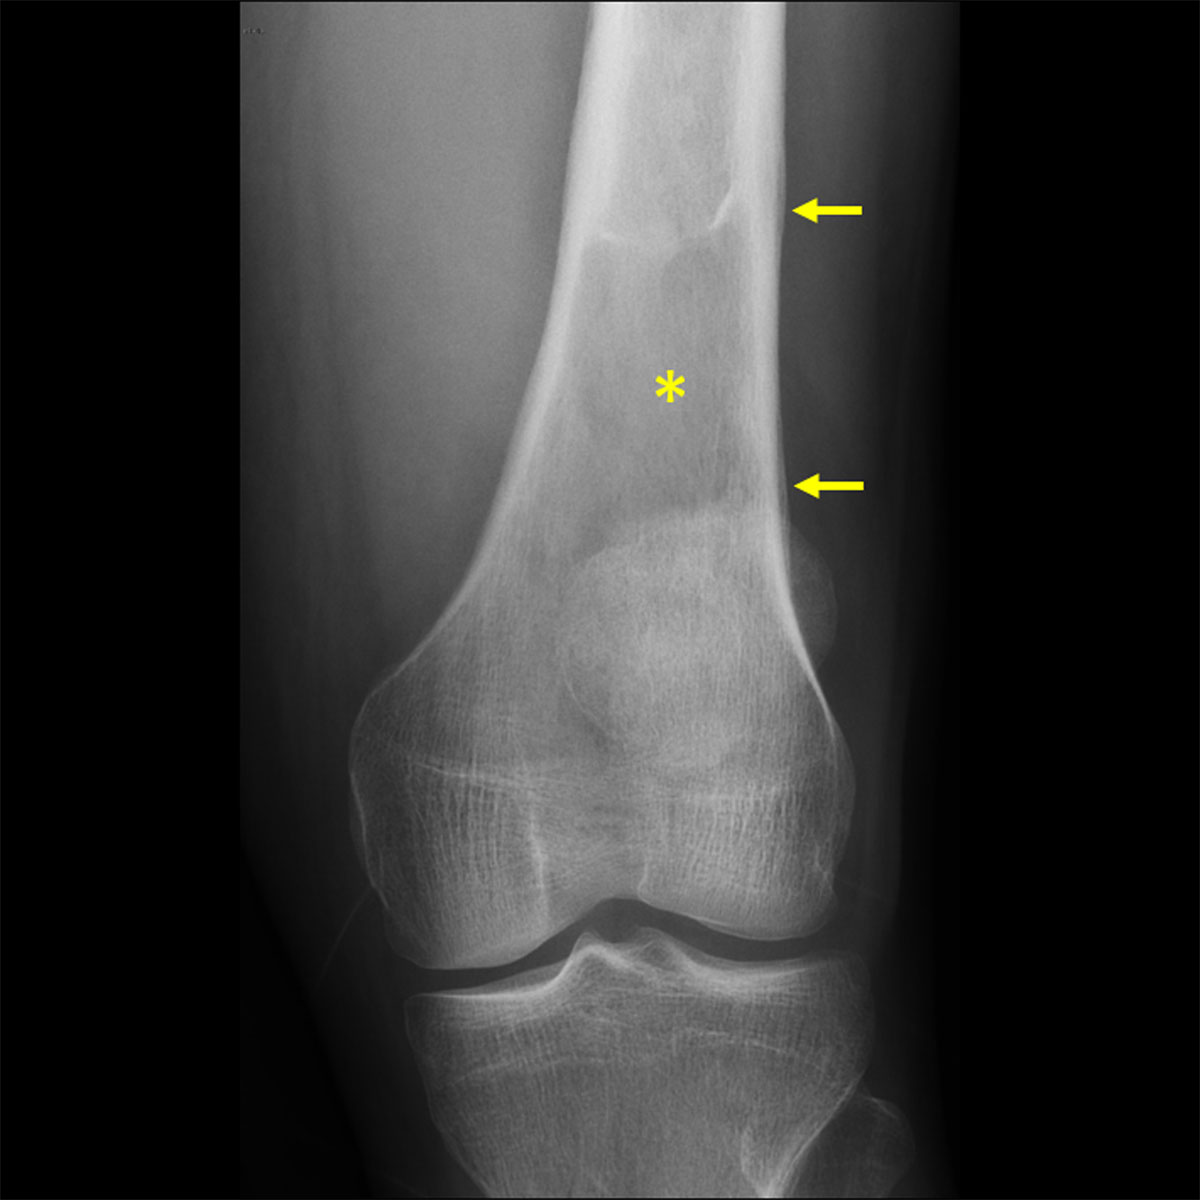

The patient underwent a knee radiograph that showed a lytic bone lesion in the femur (asterisk in Figure 1) with lamellated periosteal reaction (arrows in Figure 1). Computed tomography (CT) of the knee showed loss of the normal trabeculation of the femur’s medulla (asterisk in Figure 2A), with preserved integrity of the cortex. Periosteal reaction (arrow in Figure 2A) and densification of the adjacent soft tissues (arrowhead in Figure 2B) were noticed.

Figure 1

Knee radiograph showing a lytic lesion in the femur with lamellated periosteal reaction.